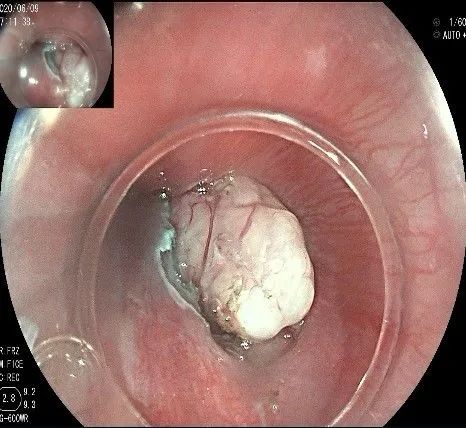

倒镜观察,可见贲门部一个明显的隆起,中央部分的凹陷,是4天前取活检留下的。

我们的思路:病变长径约2.0cm,位置活动,倒镜后先在胃底侧粘膜下注射,使病变向食管腔方向抬举,然后再在食管腔内做粘膜下注射切开,以获得一个好的术野,果然,注射后粘膜抬举明显,瘤体被挤向口侧。

正镜观察,瘤体就在贲门部齿状线的下方。

在食管腔内,瘤体的两侧行粘膜下注射后,在瘤体顶部纵向自口侧向肛侧切开食管粘膜。